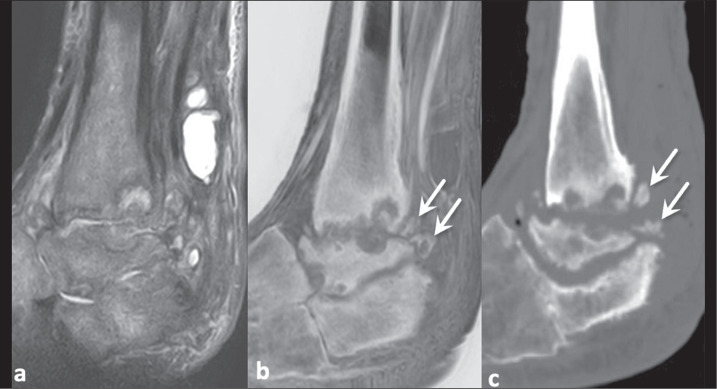

Increasing tissue contrast for bone assessment on magnetic resonance imaging has been the aim of several recent studies, and various techniques have been proposed for that purpose, including ultrashort echo time sequences, zero echo time sequences, and gradient echo sequences in various acquisition forms. In this article, we discuss the fast field echo resembling a computed tomography using restricted echo-spacing (FRACTURE) sequence, which we have started to use routinely in our practice. The FRACTURE sequences are based on the acquisition of gradient echo sequences with different echo times and specific postprocessing. Gradient echo sequences are widely available on magnetic resonance imaging scanners, which is an advantage for the use of a FRACTURE sequence. However, being more susceptible to metal artifacts, a FRACTURE sequence is of limited utility in patients with metallic implants or medical devices. The aim of this article is to illustrate the use of FRACTURE sequences in various contexts, including osteoarticular infection, inflammatory arthropathy, bone tumors, fractures, and crystal deposition diseases.